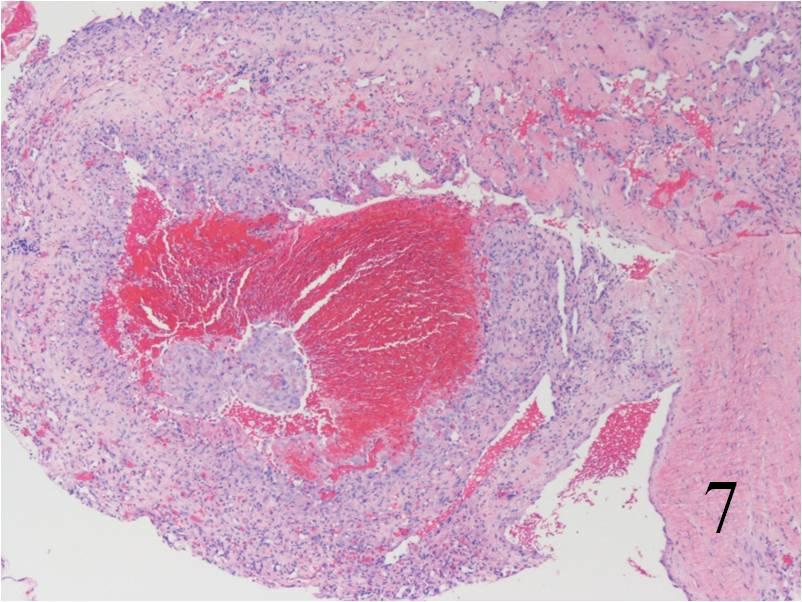

Fig. 7

Fig. 8

Fig. 7-8: Microscopic: Low (Fig. 7) and high (Fig. 8) power histology of an angiosarcoma shows abundant round to polygonal tumor cells. Fig. 8 shows nuclear atypia with mitotic activity. The cells are large with large irregular nuclei and significant pleomorphism. The cells appear somewhat epithelioid. The tumor stains positive for vimentin, Factor VIII and CD 34 (not shown in these photographs)